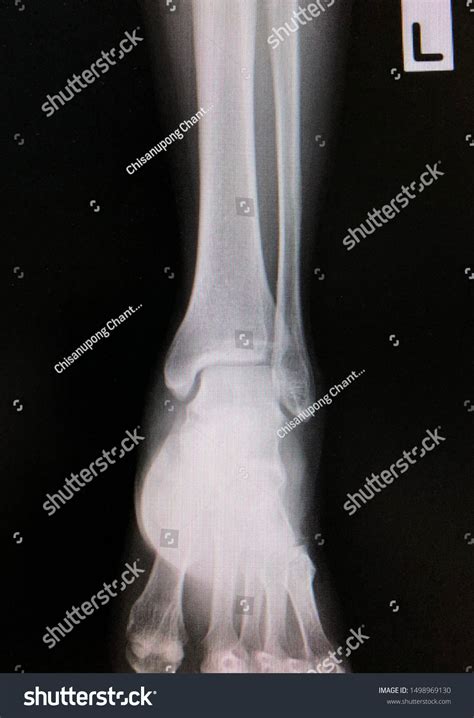

A Normal Ankle Xray is a radiographic image of the ankle joint that shows the bones, joints, and surrounding soft tissues. It is commonly used to diagnose fractures, dislocations, and other abnormalities in the ankle. The procedure is non-invasive and relatively quick, making it a preferred method for initial assessments.

3. Multiple images are taken from different angles to provide a comprehensive view of the ankle joint.

A Normal Ankle Xray typically shows the following structures clearly:

• Tibia and fibula (the two bones of the lower leg)

• Talus (the bone that forms the ankle joint)

• Calcaneus (the heel bone)

• Joint spaces and cartilage

In a normal X-ray, the bones should appear smooth and continuous, with no signs of fractures or dislocations. The joint spaces should be uniform, and there should be no evidence of bone spurs or other abnormalities.

• normal ankle x ray ap